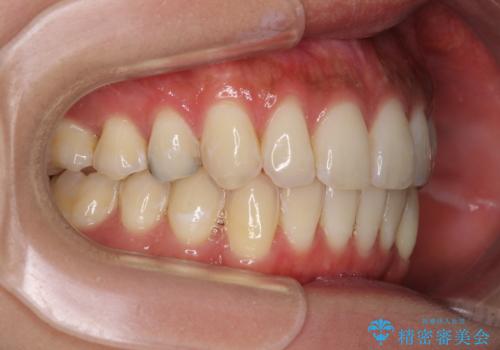

下顎の八重歯が上顎歯列に収まる過程で咬みにくさがありましたが、最終的には、咬み合わせも安定し、きれいに歯列を整えることができました。

矯正治療後には根管治療を行った歯の補綴治療を行うこととしました。